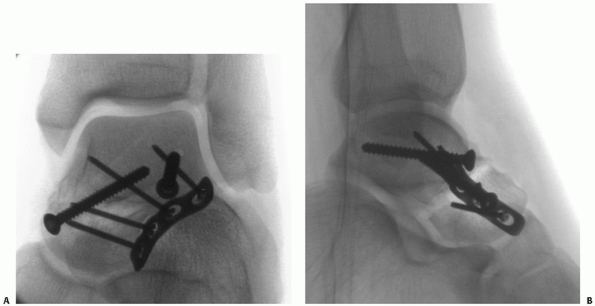

FIGURE 58-15 Anteroposterior (A) and lateral (B)

intraoperative views of talus fracture fixation. Periarticular lateral plate fixation is demonstrated, using a 2.4-mm plate extending from the anterior margin of the talar head to the lateral process. This plate is spanning a comminuted talar neck fracture with medial bone loss. An anteromedial screw was used to stabilize the medial column and a supplemental anterolateral screw was used to stabilize a large lateral process fragment. |

Screw insertion should be directed perpendicular to the plate. Good

fixation through the plate is usually achieved (see Fig. 58-15).